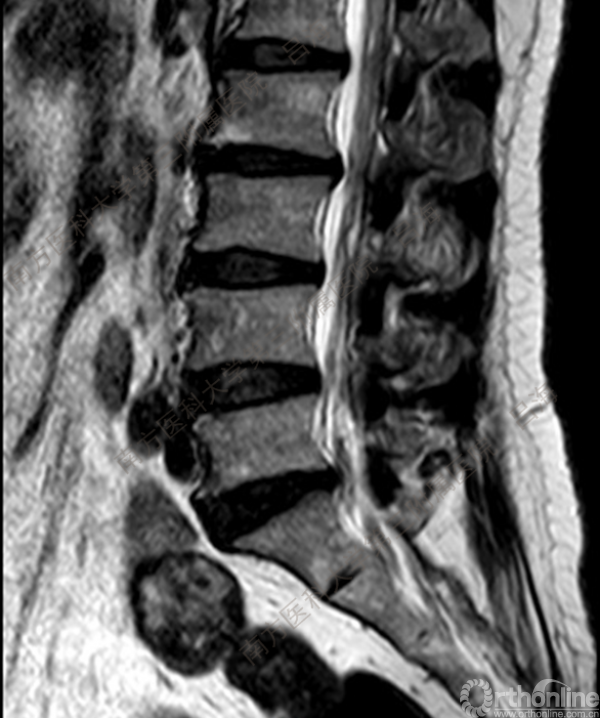

随着社会老龄化进程加快,胸腰椎退行性病变的治疗已经成为脊柱学术界的一个热点话题。MIS-TLIF手术可以治疗多种不同的胸腰椎退行性疾病,南方医科大学第三附属医院吕海教授结合病例为我们一一展示了该术式在治疗不同胸腰椎疾病时的具体手术过程。